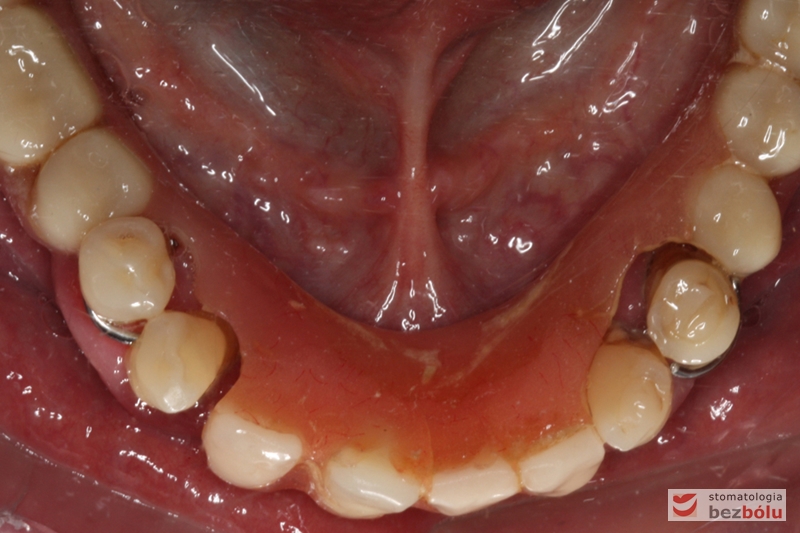

Widok łuku dolnego przed leczeniem